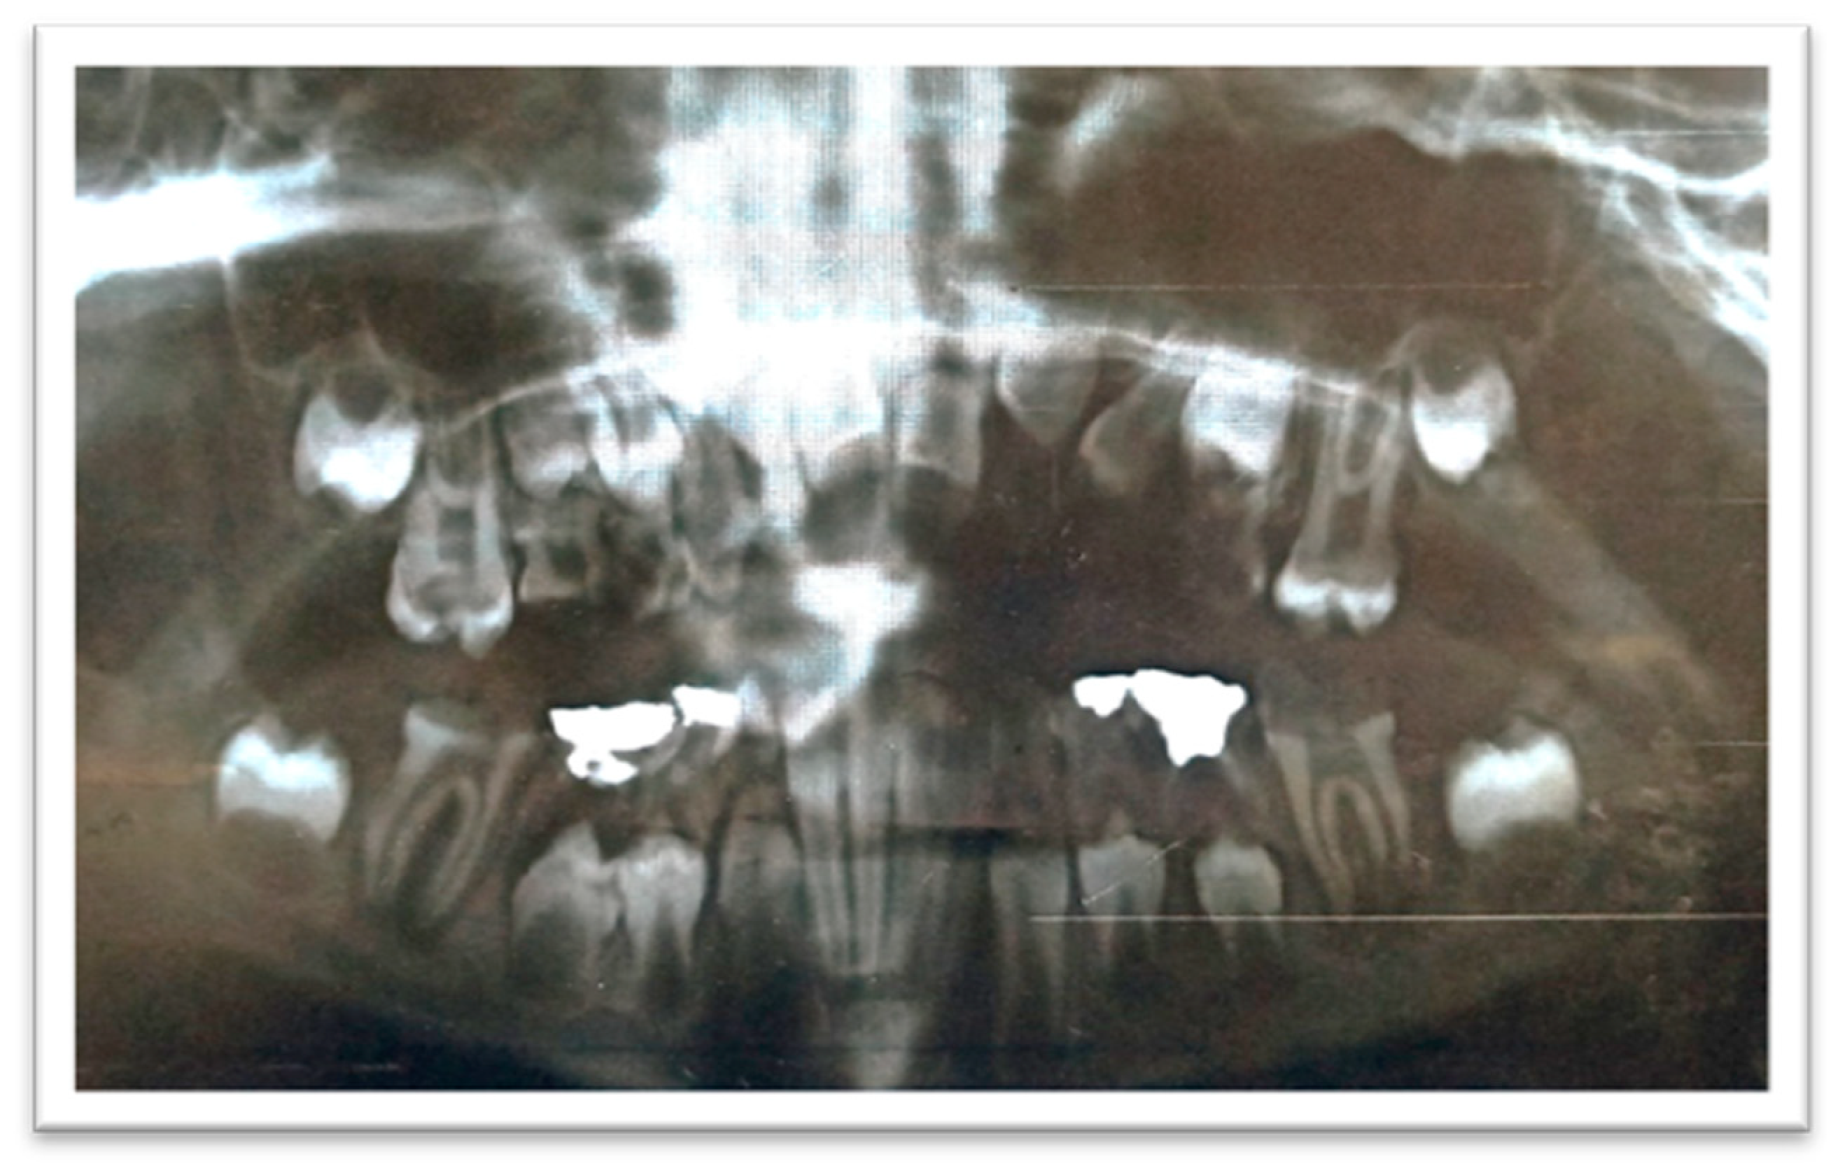

The radiographic examination showed the absence of the upper-left lateral incisor bud, multiple carious teeth, and apical lesions affecting multiple teeth, including the lower permanent first molars (Figure 3).

Figure 3.

A panoramic radiograph showing teeth #46 and #36 with extremely large carious lesions and periapical radiolucencies, tooth #16 with an extensive carious lesion, and large carious lesions in the upper primary molars.